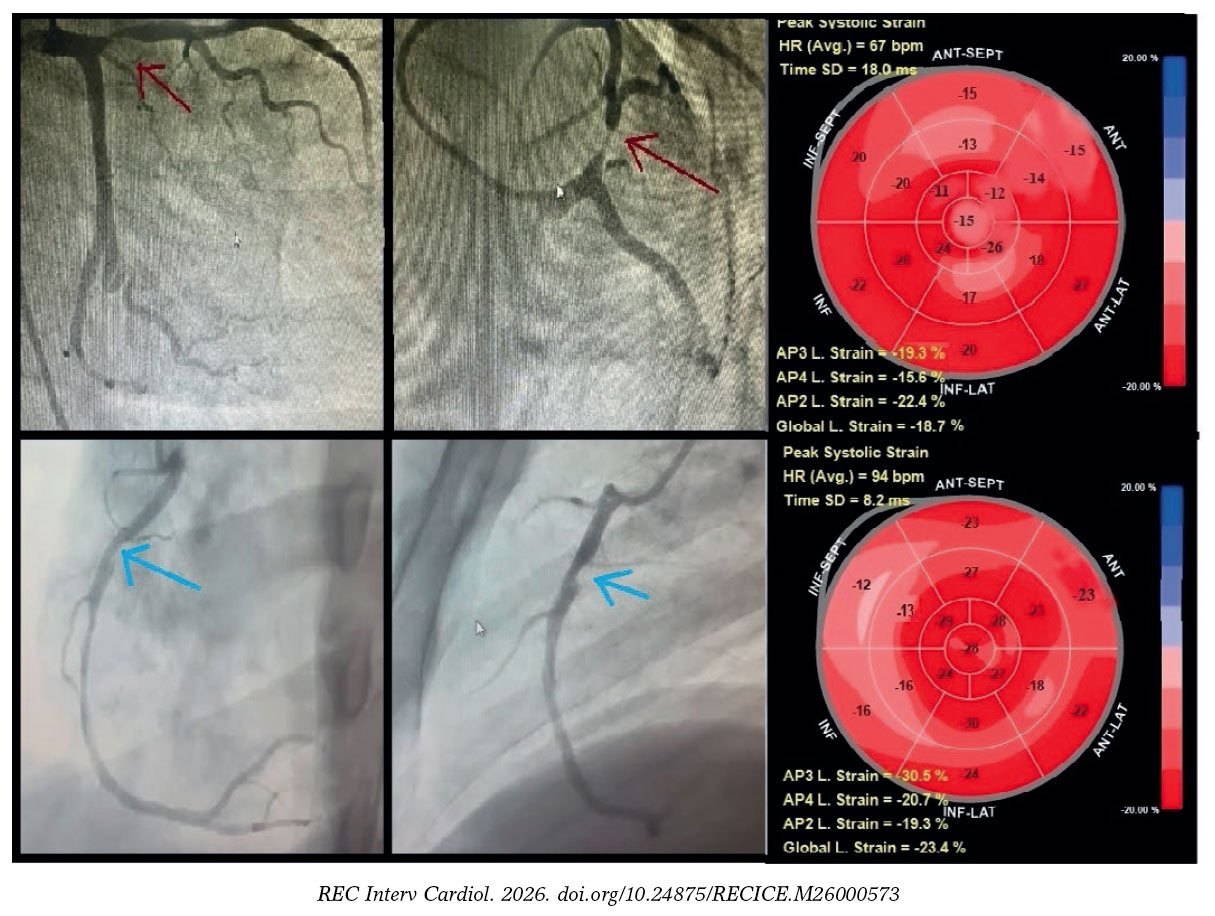

Guided by the detected cutoff of ≥ -16% for the optimal sensitivity and specificity of RLS, the predictive role of TLS in stable CAD for identifying the location and severity of significant coronary artery lesions with ≥ 70% diameter stenosis was explored (table 4). The ROC curve analysis of the RLS at a cutoff of ≥ -16% demonstrated that the optimal number of impaired segments that could predict the location and severity of significant coronary lesions with ≥ 70% diameter stenosis was ≥ 3 impaired segments out of the 7 territorial segments of LAD to predict proximal or significant lesion in the mid-LAD and ≥ 3 impaired segments among the 5 territorial segments of either the LCx or RCA to predict proximal significant lesion in the LCx or RCA (figure 4).

Figure 4. Territorial longitudinal strain of study participants with stable coronary artery disease. Top row: representative study participant with significant proximal left anterior descending coronary artery lesion (≥ 70% diameter stenosis; red arrow). Global longitudinal (L) strain was -18.7%. Seven segments within the left anterior descending coronary artery territory (anteroseptal, anterior regions, and apex) demonstrated impaired strain (≥ -16%), consistent with a true-positive finding, whereas left circumflex and right coronary artery territories showed preserved strain (< -16%), consistent with true-negative findings. Bottom row: representative of a study participant with a significant proximal right coronary artery lesion (≥ 70% diameter stenosis; blue arrow). Global longitudinal strain was -23.3%. Four segments within the right coronary artery territory (mid, basal inferior, and inferoseptal) demonstrated impaired strain (≥ -16%), consistent with a true-positive finding, whereas left anterior descending artery and left circumflex artery territories showed preserved strain (< -16%), consistent with true-negative findings.